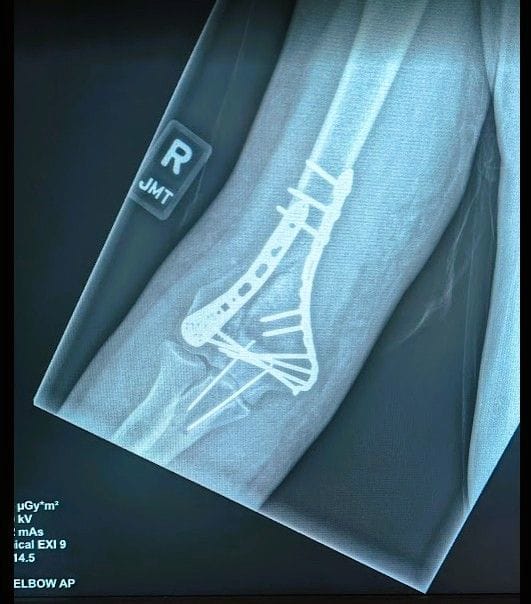

Rather than getting up, I wanted to lie there, at least for a while. (I didn’t know I was bleeding until well after hitting the ground). I was bleeding from my elbow (compound fracture with part of the bone breaking through the skin). Even slightly moving my right arm, I could feel multiple parts moving. The bones were not in the right place and felt like they were grinding against each other.

Care in the emergency room was great, but the pain was back, and I wasn’t getting laughing gas for this pain. Instead, they gave me something to sip. Perhaps this was morphine. I also remember the word codine. In the emergency room, they made me as comfortable as possible, except for the X-ray and CT scan visit. They wanted a clear picture of what they were doing, and the technician would not allow my pain to get in the way of a great picture. Sometime after the X-ray, I got to see Dr. Abdula, who helped straighten out the mess in my elbow by pulling on my arm before he put me in my first cast. This was more painful than the X-ray by a wide margin.

Don’t break your elbow. It is tough to recover from this injury. It was six weeks before I could use my right hand to operate my computer mouse. Even holding something in my right hand was difficult. The doctors seem happy with my recovery, and unlike the last eight weeks, I can actually touch my nose with my hand, getting just enough range of motion at my elbow to do something other than stretching exercises. So far, they don’t want me to lift anything heavier than a coffee cup, which is fine since I can’t eat or drink with my right hand anyway.

Wow! What a crazy X-ray. I hope you heal up fast!